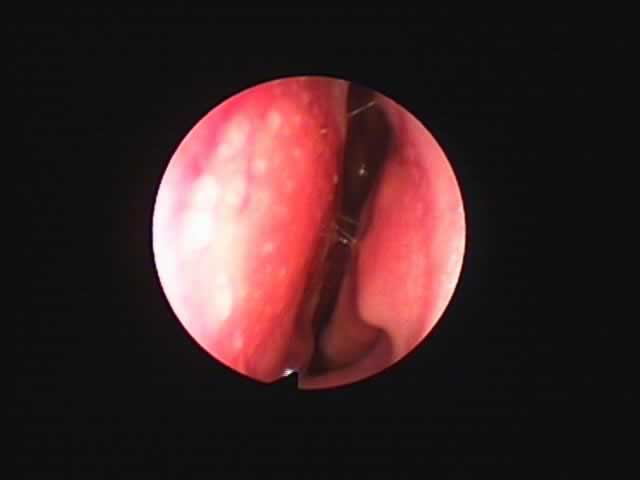

![]() |

| 7月16日 かなり縮小 | 両手術直後(縮小不十分なため追加焼灼、8月9日) | 9月8日 著明に縮小しいびき消失しているとのことです |